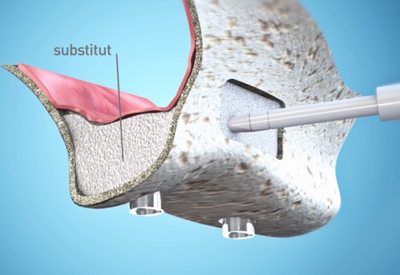

Implantologie dentaire

Un implant dentaire est une vis en titane ou en zircone totalement biocompatible. Il joue le rôle de racine artificielle et remplace une dent manquante. Il sert de support à une couronne céramique, un bridge ou de point d’ancrage à une prothèse dentaire amovible.

Les implants dentaires constituent une solution extrêmement prévisible, avec des études sur le moyen et le long terme montrant des taux très élevés de réussite.